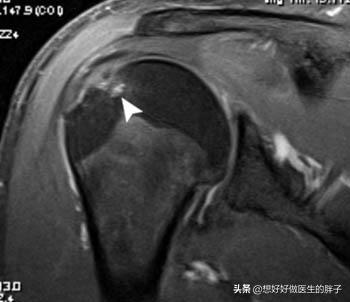

而如果要确定肩关节内的肌腱是否存在损伤,那单纯的x线就无法解决我们的问题了,我们应该进行肩关节核磁的检查,明确肩关节内软组织是否存在明显的撕裂或者是损伤?肩关节是否有积液?肌腱的位置是否正确?(下图就是肩关节撞击综合症导致肱骨大结节的囊变的,肩袖肌腱的退变核磁影像)